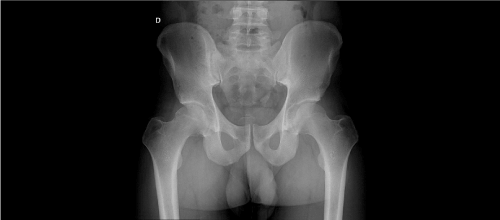

Four of our patients’ preoperative pelvic radiographs (66.6%) showed no calcifications, which made diagnosis difficult (Figure 1A, 1B). All patients’ preoperative MRI showed synovial hyperplasia and cartilaginous masses, which highly suggested the diagnosis of chondromatosis (Figures 2a, 2b).

Figure 2a. Coronal T1-Wieghted image (Left)

Figure 2b. Axial T1-Wieghted image (Right) showing hyperintense masses highly suggesting of synovial chondromatosis of right hip